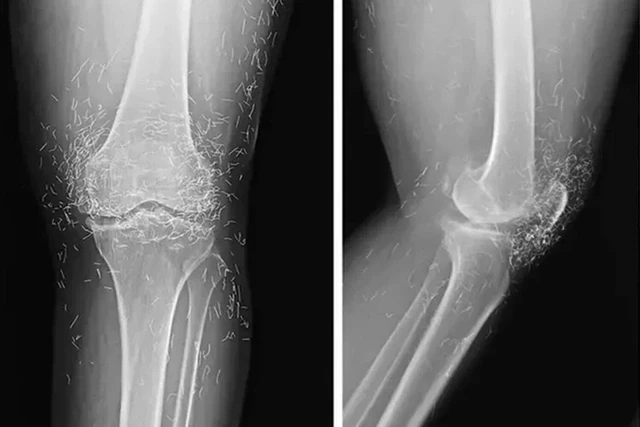

Rentgen müayinəsi zamanı sümüklərin qalınlaşması və deformasiyası, osteoartritin tipik əlamətləri, eləcə də diz oynağının ətrafındakı toxumaya yerləşdirilmiş yüzlərlə qızıl fraqmentlər müəyyən edilib.

32gun.az "Oddity Central"a istinadən xəbər verir ki, müayinə zamanı həkimlər gözlənilməz halla üzləşiblər - qadının ayaqlarında yüzlərlə xırda xalis qızıl sap aşkar edilib.